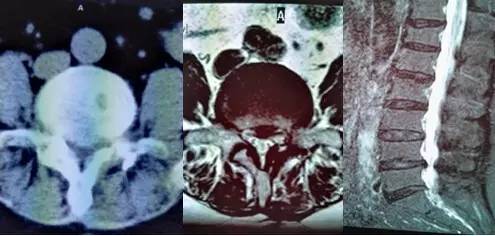

术前CT、MRI(磁共振)示:腰4、5椎间盘突出及椎管狭窄,硬膜囊严重受压变形。

入院后经过详细询问病史,全面、仔细体格检查,认真阅读患者腰椎X片、CT和磁共振检查及其它辅助检查结果后发现:患者系老年(69岁)、女性,10年前因“腰椎间盘突出症”曾在重庆某大医院进行过手术,有糖尿病史2年,不规则服降血糖药物治疗。此次入院前20天因背重物后出现腰腿痛及双下肢麻木,以左下肢为重,影响日常生活。下腰部压痛及叩痛明显,并向双下肢放射。左外踝及足背、足底感觉明显减退,左下肢肌力明显下降,右下肢肌力轻度下降。腰椎X片提示:腰椎骨质增生伴骨质疏松,腰4及腰5左侧椎板部分缺失。腰椎CT和磁共振提示:腰4、5椎间盘向后侧中央突出,伴同平面椎管狭窄,致硬膜囊及神经根严重受压、变形。血糖及糖化血红蛋白均明显高于正常范围。